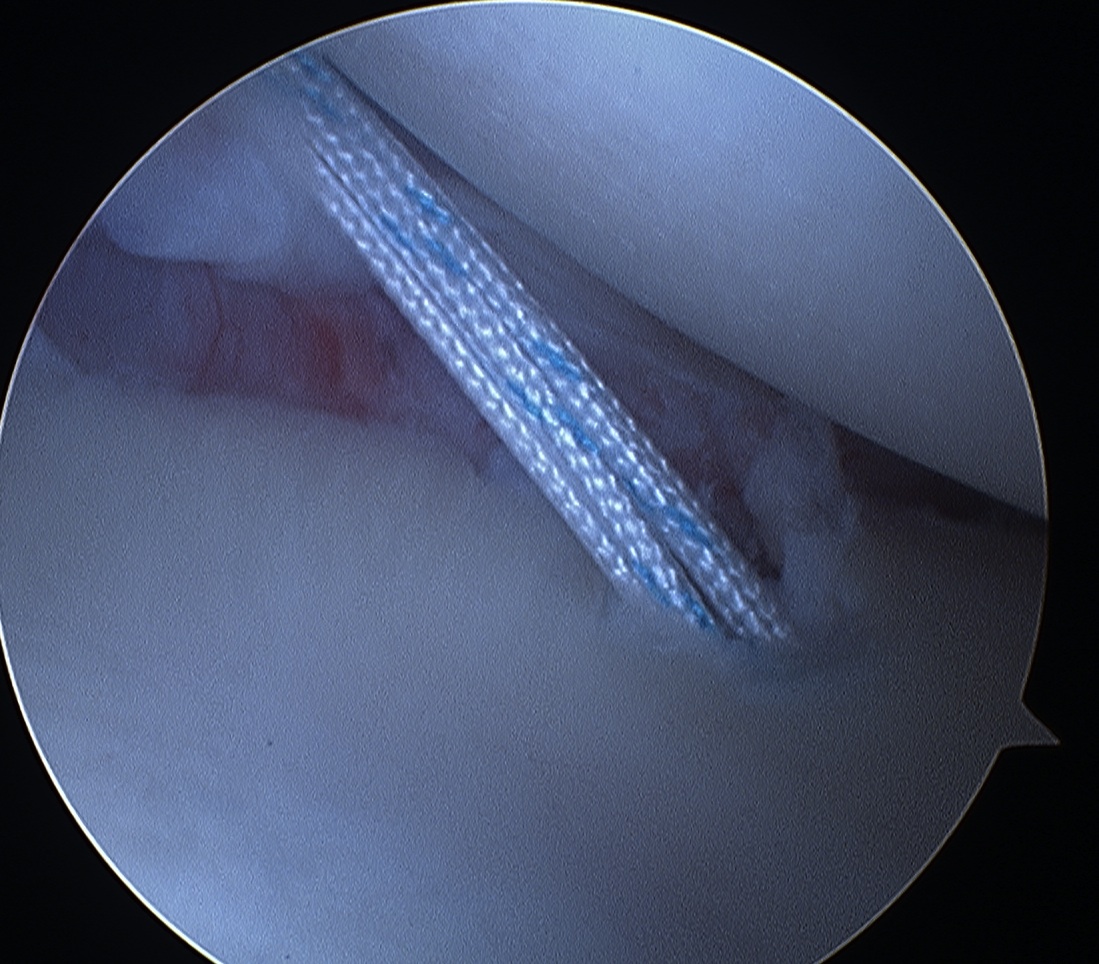

Pass sutures and tie knots

Typically curved suture passers

Aim to tighten capsule medially and superiorly onto glenoid

Shoulder Bankart Repair Suture PasserShoulder Instability inferior Suture passage

Arthroscopy Anterior Bankart RepairShoulder Bankart RepairShoulder Scope Bankart Repair 2